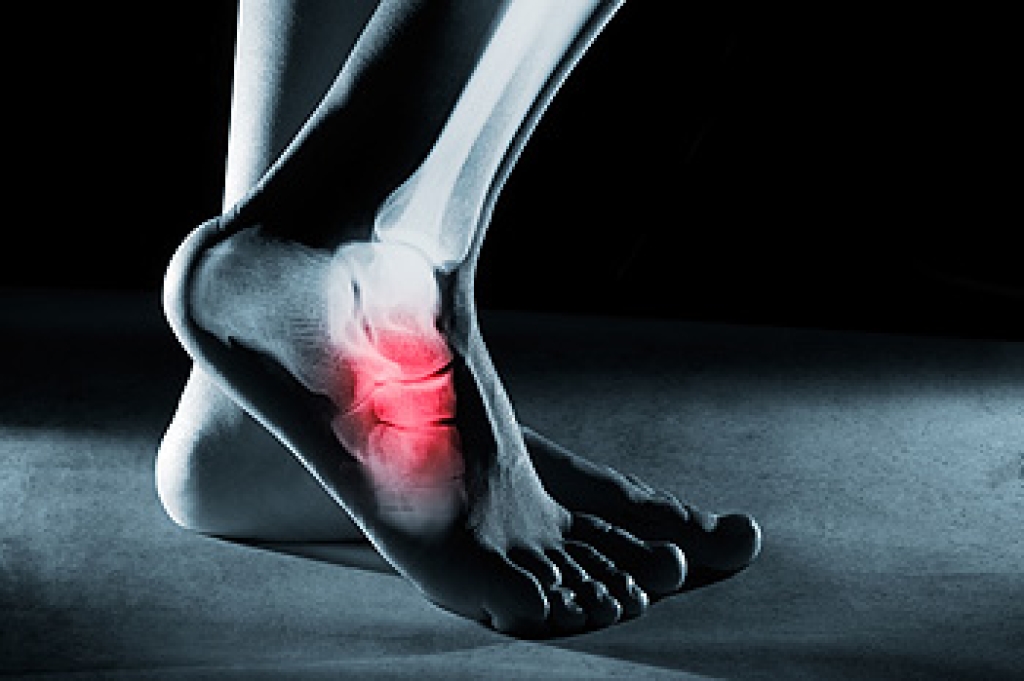

When an ingrown toenail becomes infected, it often causes redness, swelling, and pain that worsens with pressure. The area where the toenail has grown into the skin may feel warm, and fluid or pus can form as the body responds to bacteria or fungus. Infections can develop quickly and may spread deeper into the toe, if not addressed quickly. People with poor circulation or nerve damage in the feet face a higher risk of complications because healing is impaired. A podiatrist can examine the toe and confirm the cause of the infection. If necessary, the problem section of the nail can be removed safely. Care includes cleaning the area, reducing pressure on the nail, and prescribing medication, as needed. Early treatment helps prevent deeper tissue damage and ongoing discomfort. If you are suffering from an ingrown toenail problem, it is suggested that you schedule an appointment with a podiatrist for appropriate treatment.

Ingrown toenails occur when a toenail grows sideways into the bed of the nail, causing pain, swelling, and possibly infection.